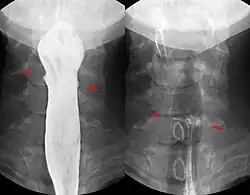

Knochensplitter oder Fischgräten können nach dem Verschlucken in die Schleimhaut des Schlunds oder der Speiseröhre eingespießt werden und dort zu Entzündungen führen. Verschluckte Fremdkörper, die in den Magen gelangt sind, gehen je nach Größe meist auf natürlichem Wege wieder ab. Bezoare (Trichobezoare, etwa eigene Haargeschwülste beim Menschen, und bei Tieren aus Pflanzenfasern gebildete Phytobezoare) können als Fremdkörper die Magen-Darm-Passage behindern.[1] Bei Knopfzellen wird die Entfernung aus dem Magen empfohlen, da eine Zerstörung der Hülle durch die Magensäure und ein Freiwerden giftigen Inhalts befürchtet werden muss. Grundsätzlich ist eine Entfernung bis in den oberen Dünndarm mittels Endoskopie möglich.

Magnetische Fremdkörper: Wenn magnetische Kleinteile (z. B. aus einem Magnetbaukasten) verschluckt werden, besteht die Gefahr, dass sich diese aufgrund ihrer Anziehung zueinander oder zu einem anderen verschluckten Eisenteil festsetzen. Ein normaler Abtransport ist dann oft nicht möglich. Es kann auch zur Anziehung von zwei Magnetteilen in zwei verschiedenen Darmschlingen kommen, so dass es dazwischen zu einer Druckschädigung des Darmes in kurzer Zeit letztlich mit Darmperforation desselben kommt. Daher wird eine gesondertes Vorgehen bei Verschlucken von mehr als einem magnetischen Fremdkörper empfohlen, was in vielen Fällen auch die operative Entfernung der Magnete einschließt.[3][4]